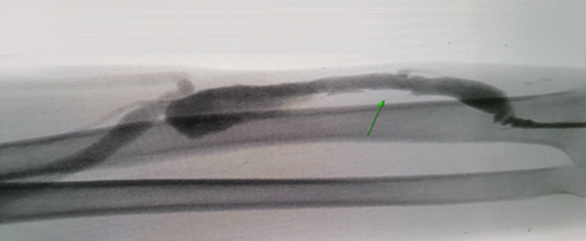

비수술적 치료(혈관중재술, 풍선시술)

투석혈관에 이상이 생겼을때 가장 먼저 시행하는 치료로써

영상장비를 이용하여 치료해 경피적 혈관성형술(PTA, percutaneous transluminal angioplasty)이라 불립니다.

참하지외과는 혈관외과 전문의가 직접 비수술적 치료를 시행합니다.

투석혈관을 직접 만드는 혈관외과 전문의가 혈관을 치료하기 때문에 의뢰받아 시술만 하는 의료진보다 정확할 수 밖에 없습니다.

풍선시술 시술 전

투석혈관 관리와 치료하기 투석혈관